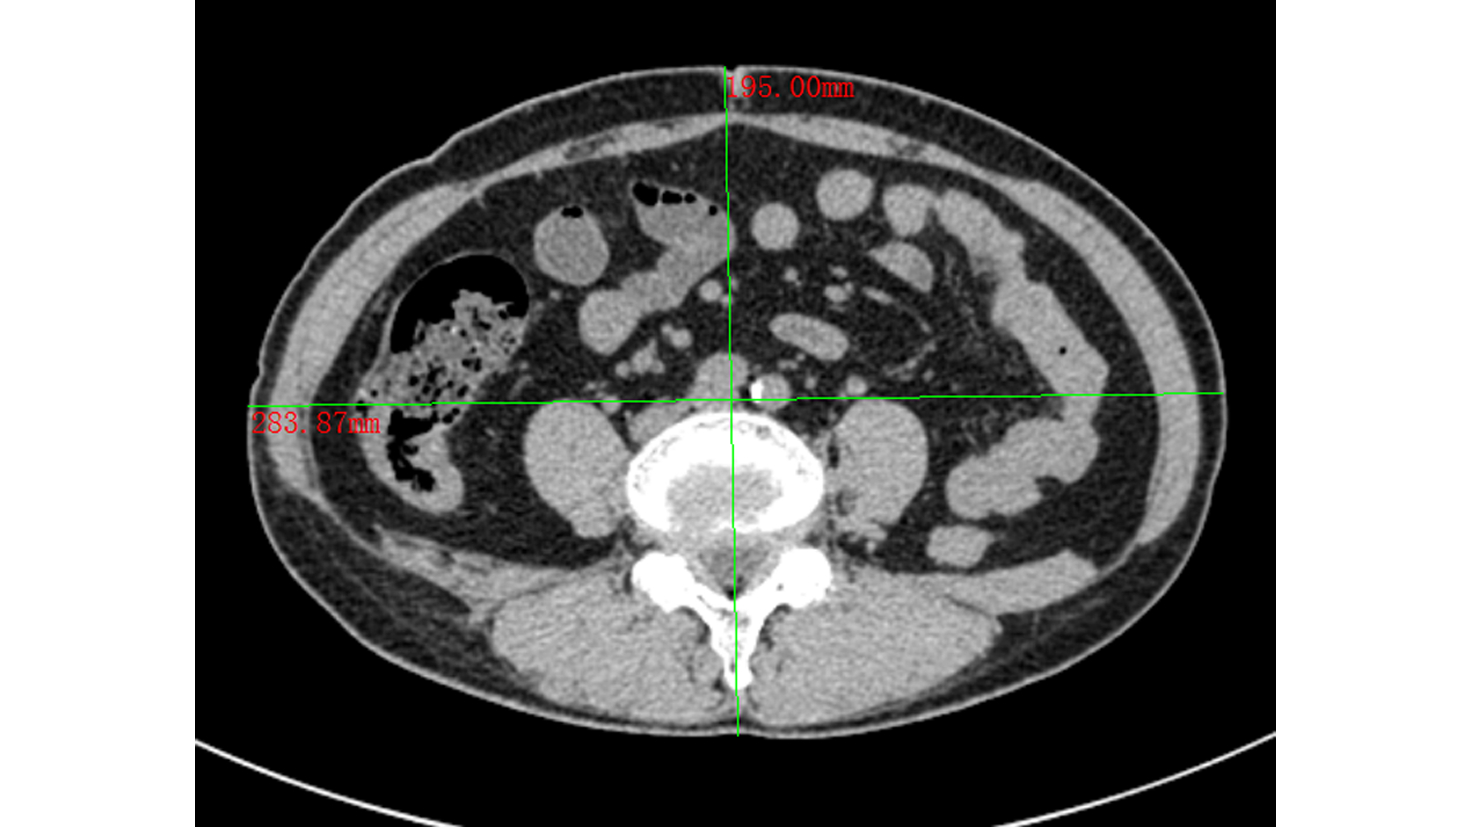

可切除胰腺癌术前评分分级体系的建立与应用

王成方, 王之江, 王伟林

2022, 38(10): 2325-2333. DOI: 10.3969/j.issn.1001-5256.2022.10.023

摘要(1021) HTML (589) PDF (2058KB)(81)

摘要:

目的  探讨分析可切除胰腺癌早期复发的危险因素及评分分级体系的建立与应用。  方法  采用回顾性病例对照研究方法,纳入浙江大学医学院附属第二医院肝胆胰外科2015年3月—2021年6月行根治性切除手术的可切除胰腺癌患者303例,其中283例直接手术患者分为早期复发组(术后6个月内)(n=95)和非早期复发组(n=188);术前行新辅助治疗患者20例为新辅助治疗组。观察指标包括患者的一般资料及术前影像资料;患者术前实验室检验资料,血常规、血生化及衍生指标,肿瘤标志物及凝血指标;随访获得无复发生存情况。正态分布的计量资料两组间比较采用t检验;非正态分布的计量资料两组间比较采用Mann-Whitney U检验。计数资料两组间比较采用χ2检验。通过受试者工作特征曲线确定各指标的最佳临界值。采用多因素Logistic回归分析胰腺癌患者早期复发的危险因素。绘制Kaplan-Meier曲线并采用Log-rank检验比较各组患者的无复发生存期。  结果  单因素分析结果显示,与非早期复发组相比,早期复发组患者BMI、甘油三酯较低,CA19-9、CA242、CA125、血浆纤维蛋白原较高(P值均<0.05)。多因素Logistic回归分析结果显示,BMI(OR=1.150,95%CI:1.038~1.273,P=0.007)、血浆纤维蛋白原(OR=2.513,95%CI:1.355~4.663,P=0.003)和CA242(OR=2.482,95%CI:1.067~5.774,P=0.035)是可切除胰腺癌患者早期复发的独立危险因素。将BMI、CA242、血浆纤维蛋白原3项指标纳入评分分级体系,临界值分别为23.00 kg/m2、30.00 U/mL和4.00 g/L。BMI<23.00 kg/m2计为1分,否则计为0分;CA242≥30.0 U/mL计为1分,否则0分;血浆纤维蛋白原≥4.00 g/L计为1分,否则0分,总分为0~3分。对早期复发与非早期复发患者进行评分,结果显示早期复发组评分更高[2(0~3)分vs 1(0~3)分,Z=-5.339,P<0.001]。Kaplan-Meier曲线分析结果显示,不同评分组别的患者无复发生存时间比较差异有统计学意义(χ2=28.116,P<0.001),分值越高预期无复发生存时间越短。将3分定义为高危组,0~2分定义为低危组。高危组早期复发率为84.6%,低危组早期复发率为31.2%。  结论  基于BMI、血浆纤维蛋白原和CA242这3项指标建立的评分系统能够在一定程度上预测患者术后复发情况。